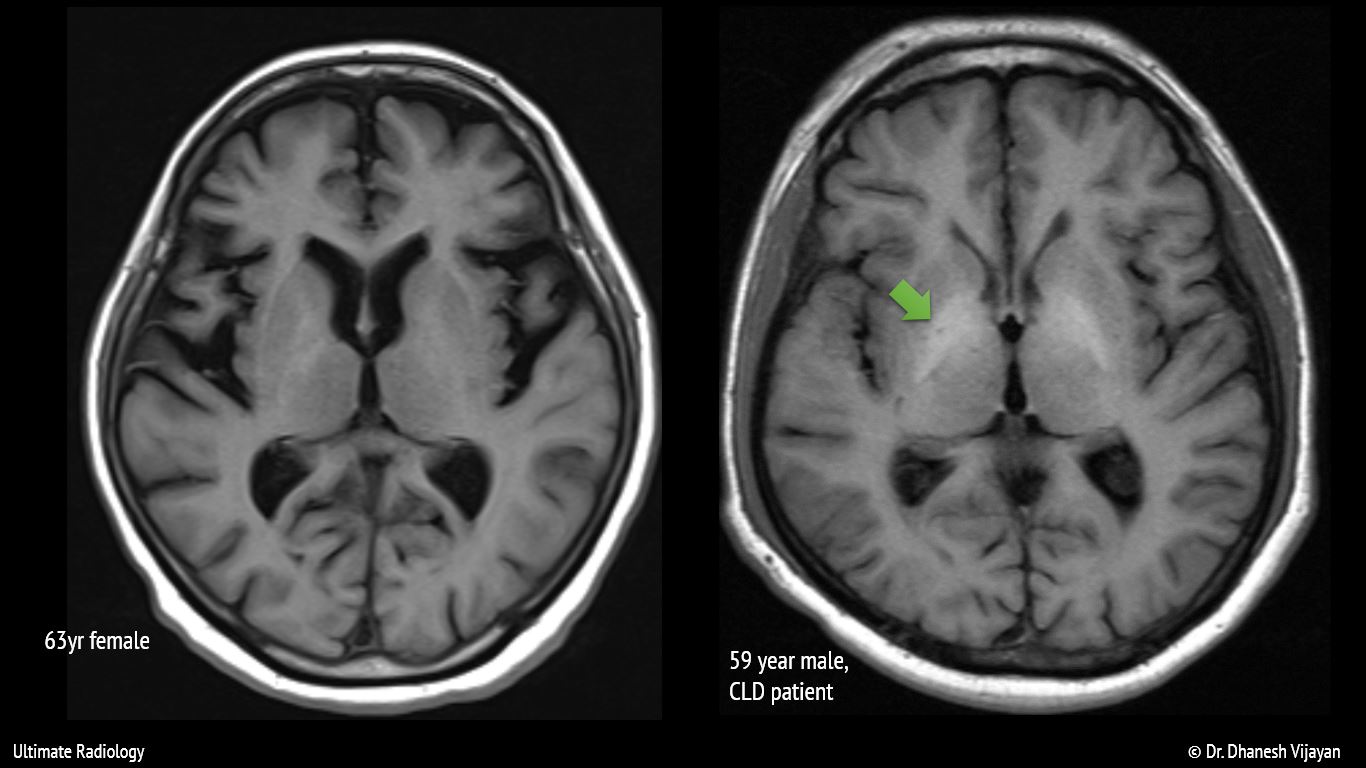

From ultimate-radiology.blogspot.com

Ultimate Radiology Bilateral basal ganglia T1 hyperintensity Basal Ganglia Damage Kernicterus regions most commonly affected include the basal ganglia; acute bilirubin encephalopathy may ensue and progress to kernicterus (chronic bilirubin encephalopathy), a permanent disabling. kernicterus is brain damage caused by unconjugated bilirubin deposition in basal ganglia and brain stem nuclei. historically, the term “kernicterus” referred to an anatomic diagnosis made at autopsy based on a. And cranial. Basal Ganglia Damage Kernicterus.